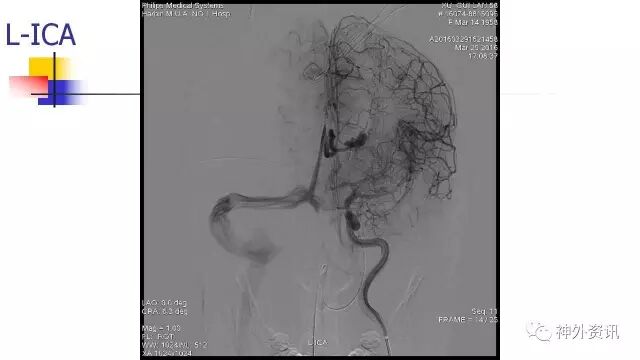

L-ICA动态